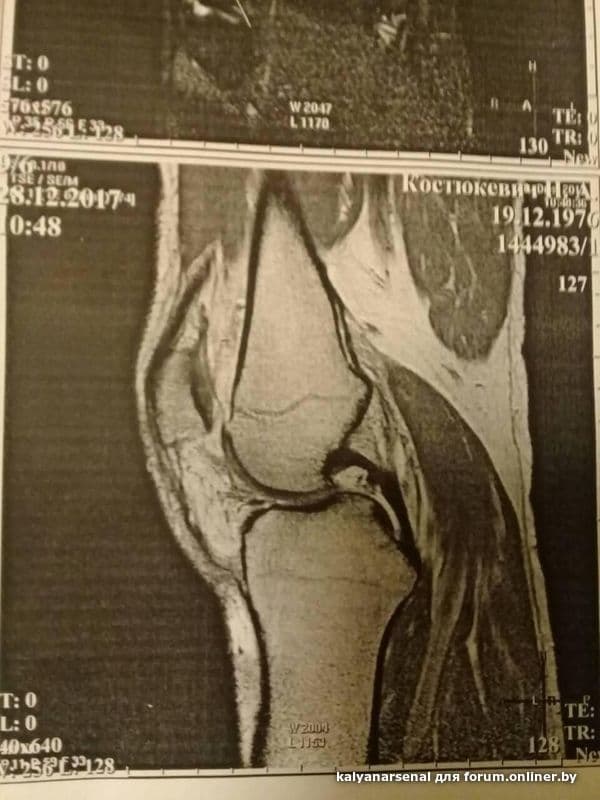

Здравствуйте,уважаемые форумчане и Дмитрий Святославович! Меня зовут Николай,мне 41год.

В общем,такая история.Всю жизнь занимался футболом, непрофессионально. И вот на последней игре выпрыгиваю я вверх за мячом,приземляюсь на одну прямую правую ногу-острая боль,полежал на газоне,отошло,попробовал бежать-бегу,но первое резкое движение в сторону-опять на газоне.Боль. Отпускает.Поднимаюсь,иду к авто,нормально,не хромая,только тяжесть в колене.Колено обычной формы и цвета. Назавтра просыпаюсь,еле ступаю на поврежденную ногу. Но ни отека,ничего такого. Как то ковыляю до работы.Нога не разгибается,полусогнута.Так и живу. Думаю,ушиб или растяжение,к врачу не иду.По-тихоньку день за днем нога выпрямляется,проходит месяц,но,чувствую,как то медленно все восстанавливается.Через 1.5мес решил сделать мрт:ВЕРОЯТНО полный разрыв пкс! Ну все,приплыли...Пошел к одному,второму специалисту-мнение у них одно:симптома выдвижного ящика нет,нестабильности и блокад нет,так что консервативное тебе парень.Прошло 4 месяца.Хожу на физиопроцедуры-лазер и ультразвук,по тихоньку занимаюсь в тренажерке-посоветовали укреплять мышцы ноги(велосипед,элепс и т.д.) Озадачивает меня,что на сегодняшний день как то я не чувствую,что идет улучшение: и по ступенькам больновато подниматься(боль за чашечкой), и при обычной ходьбе бывает ноющая боль,на корточки до конца не могу,в покое-без проблем. Много друзей кто делал пластику и не делал: одни говорят-делай,другие -не делай. 2врача-пока консервативно. На всякий сделал еще и рентген-все в порядке.Может у меня проблемка в мениске,так как за 4 мес все,что должно было срастись-срослось бы.Правильно? Получается,решение в этом случае лишь одно-артроскопия.Просто в заключении МРТ аж 2 слова ВЕРОЯТНО. Был у еще одного травматолога-ортопеда,договорились,что приду на повторный прием через месяц,а пока наказал мне при помощи лфк восстановить объем движений и эластичности коленного сустава за этот месяц и потом попробовать ногу под нагрузкой.

Пробую на месте делать ротационные футбольные движения с мячом,чувствую-могу поломаться.Ну вот вчера пробежал чуток-сегодня уже тяжесть в колене..Посоветовали мне еще сделать повторное мрт весной на другом аппарате,посмотрим.Просто один врач сказал,что как то все очень нечетко получилось:вроде повреждение есть,а сказать что полный разрыв он не может,а второй даже смотреть не стал мрт,только тесты поделал и сказал сустав функционирует,лечи без операции,одевайся. Ну вот такая история.Что бы Вы делали в подобной ситуации?Буду очень рад,если получу хотя бы краткий ответ! Спасибо!Всего хорошего.Фото мрт и снимков под спойлером.

Посмотрите,пожалуйста,мое сообщение за 15февраля. Там в конце под спойлером есть фото с заключением мрт. Спасибо